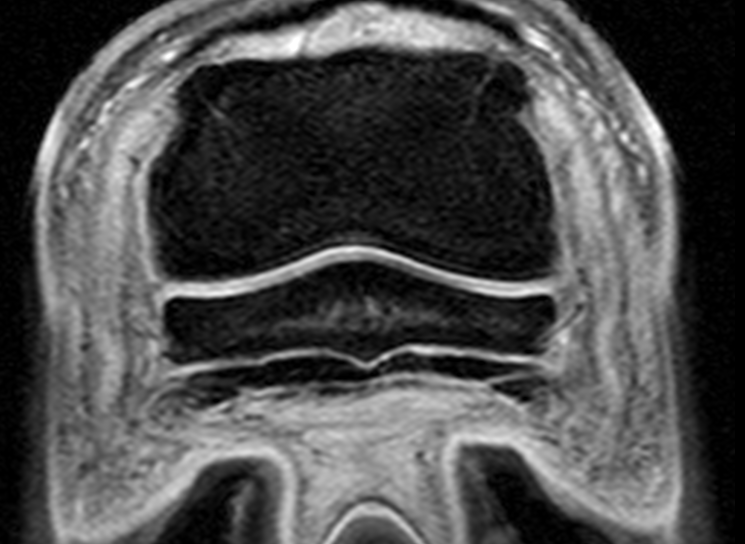

Magnetic Resonance Imaging

Chino Valley Equine Hospital is pleased to announce that we will be using the mobile MRI services of MREquine, which uses a 1.5T high field magnet.

MRI is routinely used in human medicine and is rapdily expanding to the small animal veterinary field. Progress has been made to permit larger animals, such as horses, to enter these machines.

MRI has been used to evaluate orthopedic injuries in horses in some veterinary hospitals for more than ten years. It has resulted in the diagnosis of many conditions which were previously unrecognized and has resulted in new treatments, such as navicular bursoscopy, to treat flexor tendon injuries in the hoof.

High field Systems - 1.5 Tesla Magnet - General Anesthesia

The most important factor is that the higher the field strength, the more signal emanating from the patient that is available to generate images.

High field magnets allow image acquisition faster than low field magnets and this results in reduced scan time.

From a practical perspective, having accepted the need for anesthesia, it makes much more sense to image a horse in a high field magnet than a low field magnet, as image quality will be superior, more anatomy can be covered and the study can be completed in less time, thus minimizing potential anesthesia related complications.